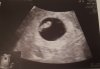

Ja już też po wizycie. Dzidziulek rośnie, ma 0,93cm (7+0). Ale pojawił się krwiak obok i mam trochę zakazów- zakaz seksu, całkowity zakaz dźwigania, dużo odpoczywać. Dostałam skierowanie na badania w szpitalu, gdzie lekarz przyjmuje, więc będą na NFZ, no i jutro kazał już umawiać się na prenatalne.

Termin porodu bez zmian 12 lipca

Załączniki

• 20201123_204115.jpg

20201123_204115.jpg

3,3 MB · Wyświetleń: 107